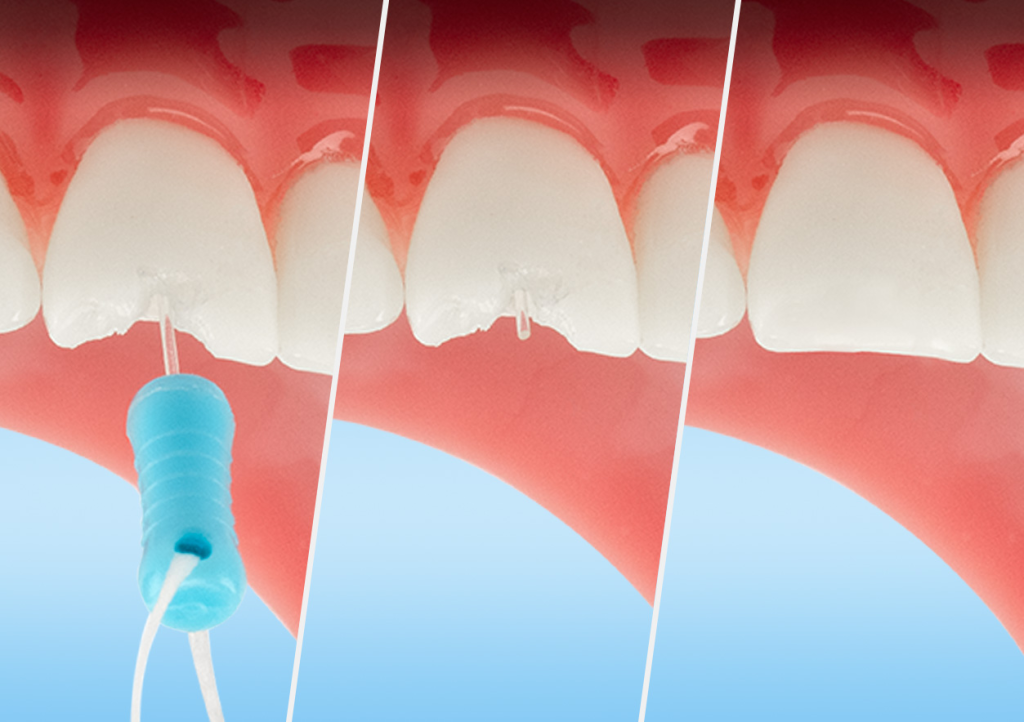

Add Floss to Pin

Be sure to attach floss to the handle of the pin to ensure it is not swallowed or aspirated during the procedure. See the picture above.

Pin Placement

The tooth is now ready for restoration with any composite system. The pin improves light-curing depth and shear strength.